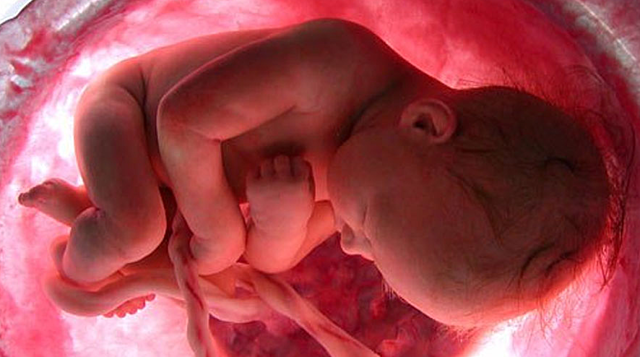

• Semana de la 28 - 29

Semana de la 28 - 29

En estas semanas de embarazo el peso del bebe es de unos 1.100 gramos y la longitud total llega a los 35 o 40 centímetros de la cabeza a los pies. El sistema nervioso central se está desarrollando mucho en estas semanas de gestación.

• Semana 30

Semana 30

El bebe ya pesa unos 1.350 gramos y mide unos 38 centímetros de la cabeza a los pies con 30 semanas de embarazo. Si todo transcurre con normalidad, la futura madre tendra que ir al ginecólogo hasta la semana 36 de embarazo, ya que las citas se dan cada cuatro o seis semanas.